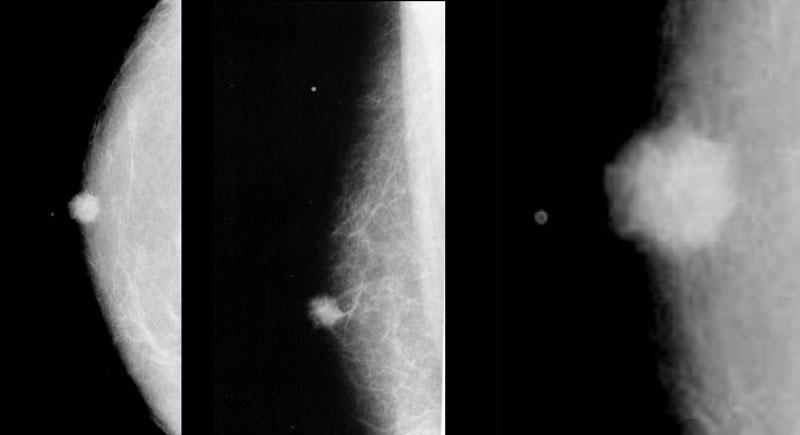

Bên trái là hình chụp nhũ ảnh vú nam giới với dạng gynecomastia thể nốt tuyến.

Có một vùng đậm độ hình quạt tỏa ra từ núm vú.

Tổn thương có thể nổi bật hơn ở góc phần tư trên ngoài và, quan trọng hơn, nó hòa lẫn vào mô mỡ xung quanh.

Nếu nhìn nhũ ảnh bên trái như là vú của một phụ nữ thay vì đàn ông, bạn có thể nhận định đây là một khối bờ không rõ và kết luận đây là tổn thương ác tính.

Tuy nhiên, ở nam giới, bờ không rõ này lại là dấu hiệu của gynecomastia.

Gynecomastia là sự tăng sinh đồng thời của các ống tuyến và mô đệm mà không có bao xơ bao quanh, do đó tổn thương phải hòa lẫn vào mô mỡ xung quanh.